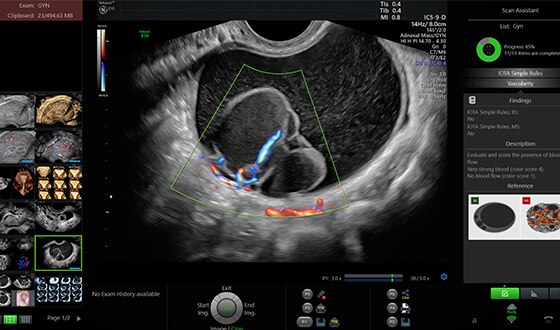

Display extraordinary image detail with Voluson’s Radiance System Architecture; its sophisticated beam formation and powerful processing give you:*

- 4X ultrasound pathways for spectacular 2D and 3D/4D images with increased penetration and clarity

- 10X data transfer rate for higher resolution and very fast frame rates

- 4X processing power for advanced applications and efficient workflow